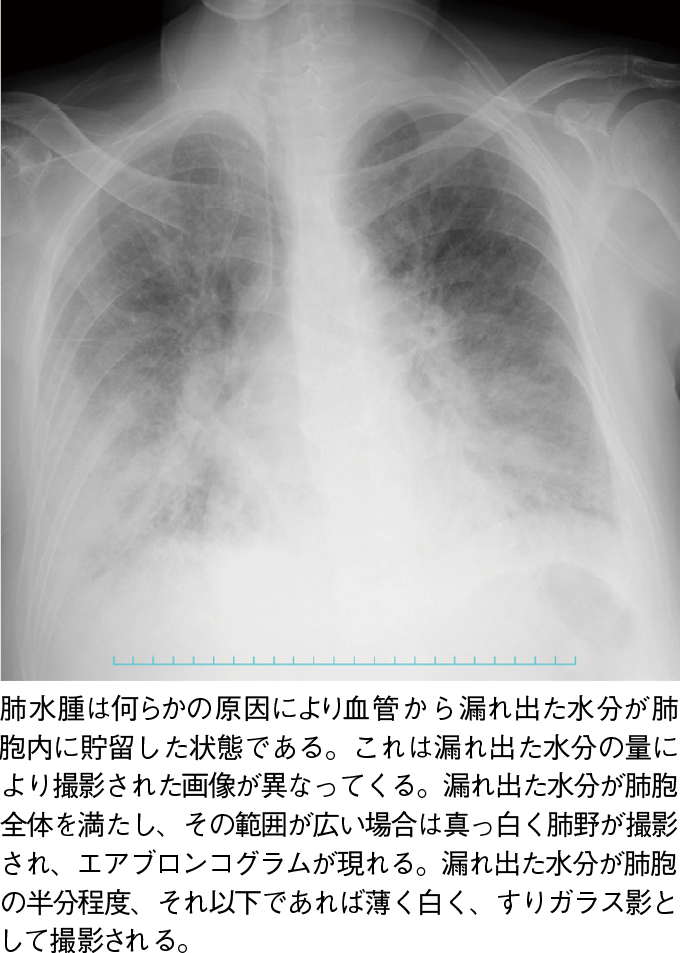

エアブロンコグラム:

肺胞内が水分でみたされると、末梢の気管支が黒く抜けて撮影される。気管支周囲の肺胞が水分で満たされることで、肺胞は白く映るが、気管支は空気で満たされており、黒く映るためである。エアブロンコグラムを見つけたときに考えることは、肺胞が水分で満たされた病態を想起することである。気管支内よりも肺胞内に炎症が集中する肺炎、肺胞内が血管からもれでた水分で満たされる肺水腫などがある。

写真6肺水腫:両側に認める肺水腫